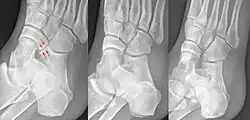

Häufigste Form der tarsalen Koalition, die kalkaneonavikulare Koalition im schrägen Röntgenbild des Fußes (links, Pfeile) mit zwei diesbezüglich unauffälligen Vergleichsfüßen. Die Koalition ist nicht knöchern, sondern bindegewebig oder knorpelig.